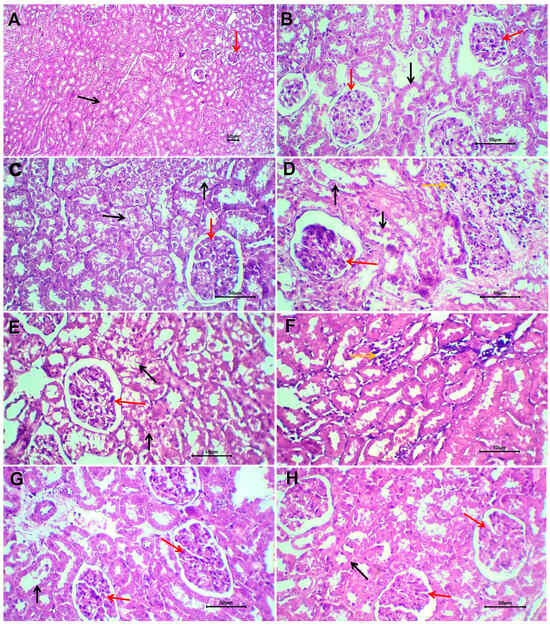

3.12. Histological Results